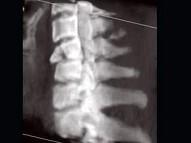

问题 男,68岁,从2米高的平台坠落后颈部疼痛6小时,结合影像学检查,最可能的诊断是?(?)

选项 A.脊椎结核 B.椎体压缩性骨折 C.脊椎转移瘤 D.化脓性脊柱炎 E.强直性脊柱炎

答案 B